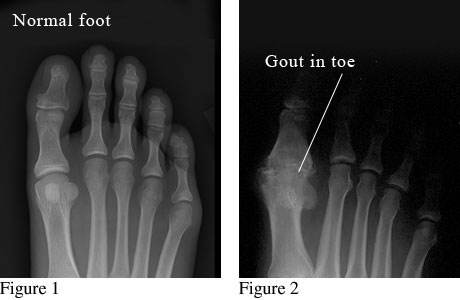

X-ray images of a normal foot and a foot with gout in the big toe

Figure 1 is an X-ray of a normal foot with healthy bones and joints.

Figure 2 is an X-ray of a deformed toe joint caused by chronic gout.